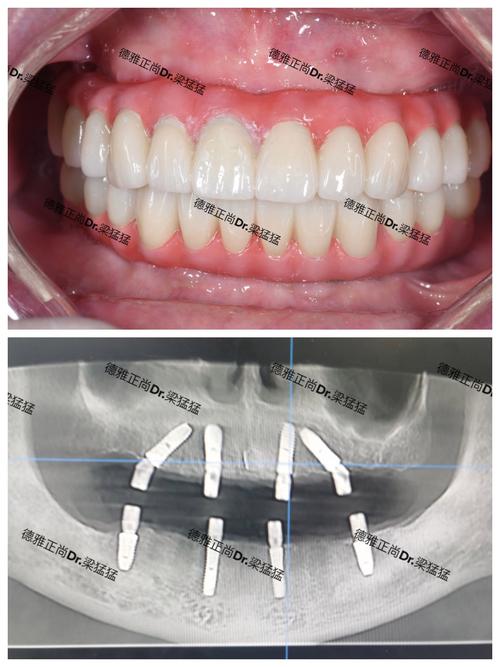

- All-on-4® 立即负重技术: 这是目前最主流、最常用的全口种植方案。仅需植入4颗种植体(上颌或下颌各4颗),后两颗种植体通常以一定角度植入,以避开重要的解剖结构(如下牙槽神经管、上颌窦),同时利用倾斜角度增加骨接触面积和抗旋转能力,从而用最少的种植体支撑起整个牙桥,实现当天或短期内戴牙(立即负重)。

- All-on-6 技术: 在骨量相对较好或希望获得更分散的咬合力分布时使用。植入6颗种植体(上颌或下颌各6颗),提供比All-on-4更多的支撑点,理论上长期稳定性可能更好,但费用更高,手术时间也可能稍长。

(图片来源网络,侵删) -